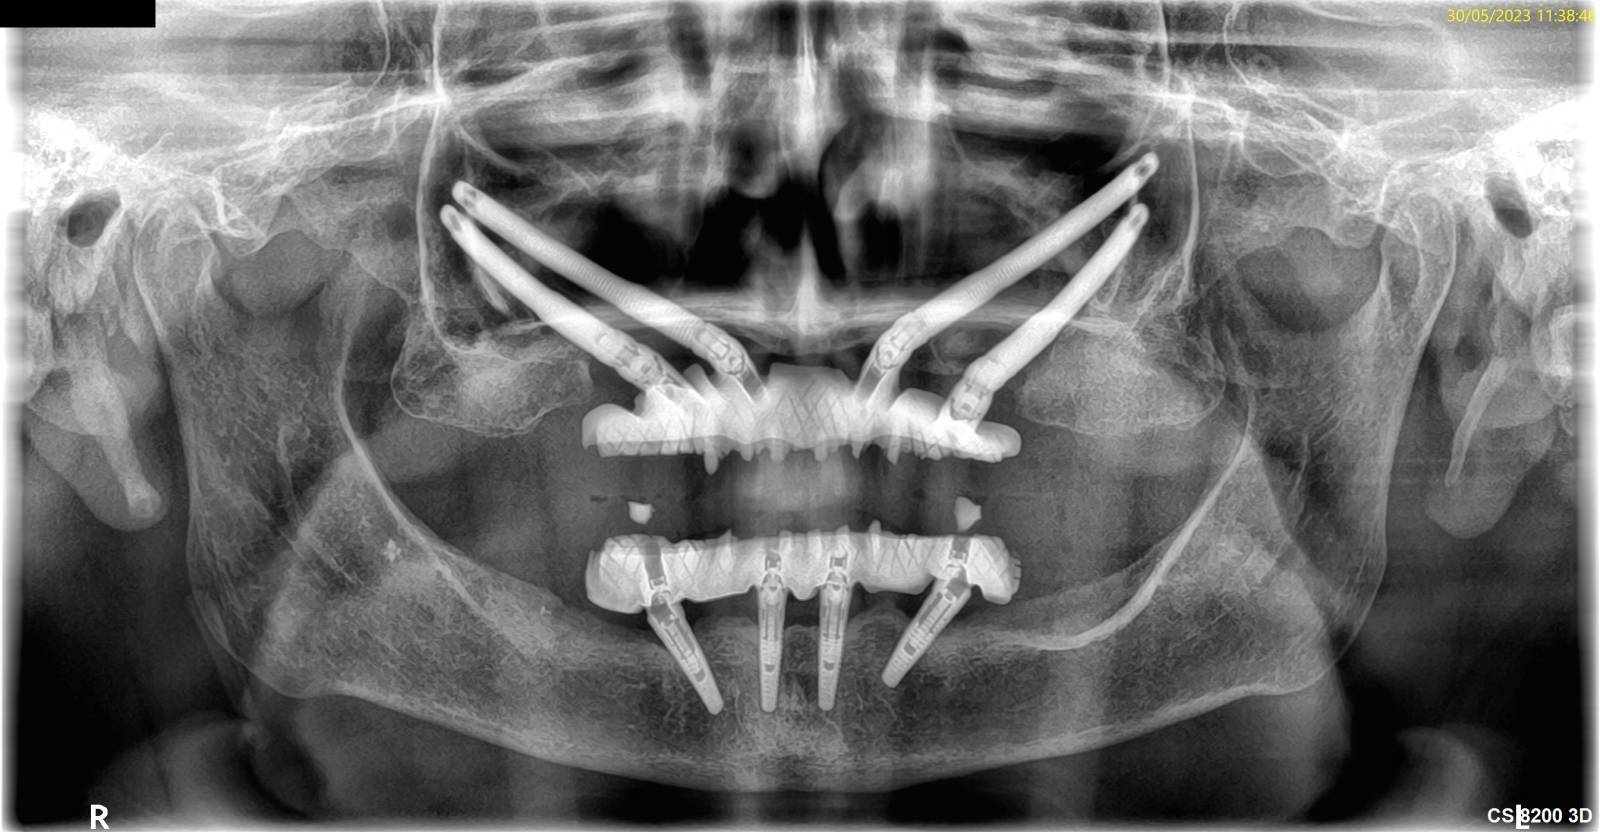

L'implant zygomatique, également connu sous le nom d'implant malaire, est une option de traitement utilisée au cabinet Implantys près de Mâcon pour ancrer des prothèses dentaires chez les patients qui ont une perte osseuse sévère dans la région maxillaire supérieure et qui ne peuvent pas bénéficier d'implants conventionnels en raison du manque de densité osseuse. L'implant zygomatique diffère donc des implants dentaires conventionnels qui sont, eux, insérés dans l'os maxillaire. Cet implant est conçu pour être fixé dans l'os zygomatique, également appelé os malaire, situé près de la pommette. Cette alternative vous est proposée par nos chirurgiens dentistes spécialisés en implantologie, au cabinet Implantys proche de Belleville-en-Beaujolais.

Le processus d'implantation zygomatique est plus complexe que celui des implants conventionnels. Il nécessite une évaluation et une planification approfondies, ainsi qu'une intervention chirurgicale réalisée par un spécialiste qualifié, comme vous en trouverez dans notre au cabinet Implantys près de Belleville-en-Beaujolais. Pendant la chirurgie réalisée sous anesthésie générale, l'implant zygomatique est fixé à l'os zygomatique de manière à fournir une base solide pour les prothèses dentaires, telles que les bridges ou les prothèses complètes.

L'implant zygomatique est considéré comme une solution avancée pour les patients qui ont une perte osseuse sévère dans la région maxillaire supérieure et qui ne peuvent pas bénéficier d'implants dentaires conventionnels. Cependant, en raison de la complexité de la procédure et de la nécessité d'une expertise spécialisée, tous les dentistes ne pratiquent pas cette technique. Si vous êtes intéressé par l'implant zygomatique, il est recommandé de consulter un spécialiste qualifié en implantologie dentaire qui pourra évaluer votre cas et vous fournir les informations appropriées. Nos praticiens du cabinet Implantys à proximité de Belleville-en-Beaujolais vous accompagnent dans ces traitements.